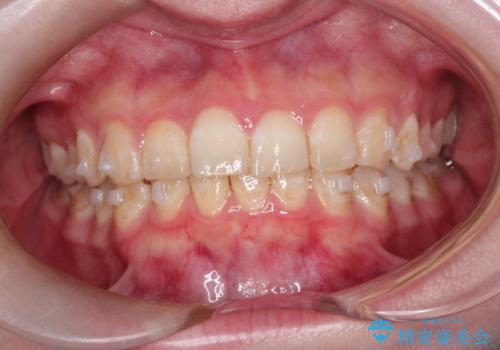

インビザラインで前歯のガタガタをきれいな歯並びへ

- 前歯のガタガタが気になるとのことで来院されました。

上顎の前歯の叢生があったのと、下あごの前歯が通常より1本欠損(先天欠損)していました。

上顎の歯と歯の間をわずかに削りスペースをつくり、並べる計画としました。インビザライン治療を選択されました。

しっかりとインビザラインを使用していただけたので、スムーズに治療を終了させることができました。